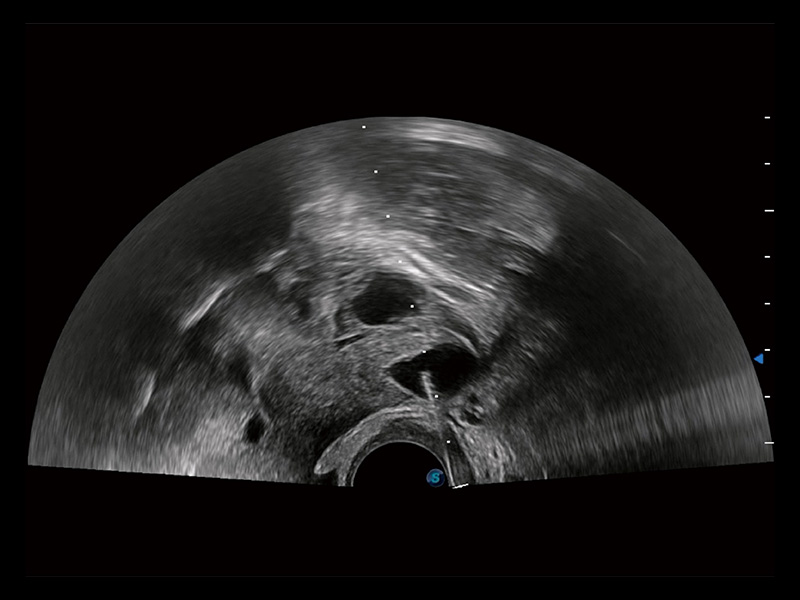

卵巢多囊样改变